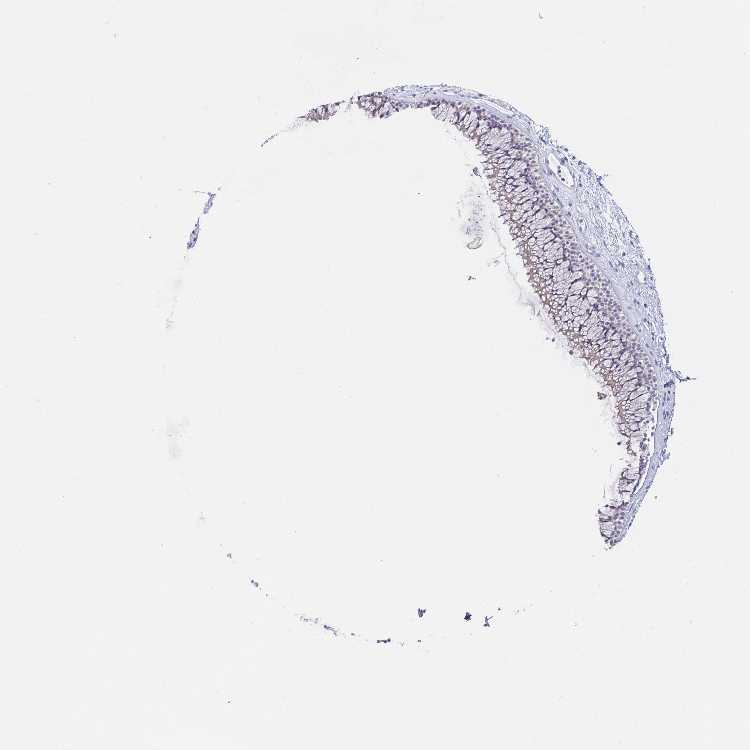

NASOPHARYNX - Antibody stainingi

Antibody staining in the annotated cell types in the current human tissue is reported as not detected, low, medium, or high, based on conventional immunohistochemistry profiling in selected tissues. This score is based on the combination of the staining intensity and fraction of stained cells.

Each image is clickable and will lead to virtual microscopy that enables deeper exploration of all samples and also displays staining intensity scores, fraction scores and subcellular localization as well as patient and tissue information for each sample.

Antibody HPA036124Antibody HPA036125Antibody HPA064821

Respiratory epithelial cells Not detectedNot detectedNot detected